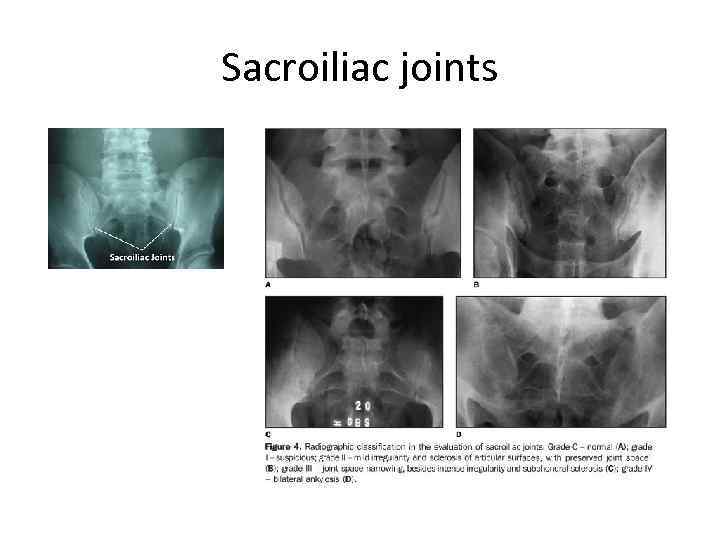

Sacroiliac joints